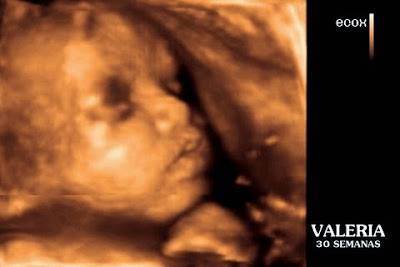

Mi experiencia en ECOX 4D y la primera vez que vi la carita de mi princesa Valeria

Os cuento cómo fue! fuimos 7, mis papis, mis suegros, mi pareja of course y Supernico! Nos recibieron fenomenal al entrar e incluso tenían una mesa para que nico jugase y colorease! Entramos y la sala era muy amplia con asiento para todos y con dos monitores! La primera vez que me lo hice la verdad en el otro centrola verdad que me miraron un poco mal cuando vieron que eramos tantos, y por supuesto todos de pie excepto la ecógrafa. En el centro de Alberto Aguilera la chica era un amor, se dirigía a mi, a Nico, y a Valeria con dulces palabras en todo momento (y eso que Nico estaba asustado...POBREEE!! me veía tumbada en una camilla y decía ·"mamá pupa" y le explicabamos que no era pupa, que me estaban echando cremita y haciendo fotos a Valeria y la veíamos en la tele! Al final salíó encantado diciendo "Valeria tele" Se la veía fenomenal aunque tendía a acurrucarse y pegarse a la pared del útero! También nos comentaron que tendría bastante pestañas ya que alrededor del ojo había una línea blanca que era "pelo y vernix"

Así que si, recomiendo la experiencia, al fin y al cabo es un recuerdo para toda la vida y también a mi me ha servido para hablar más a menudo a Nico de su hermanita que está en la tripita! Aquí un collage que nos dieron al salir a nuestro gusto con diferentes muecas de la muñequita!